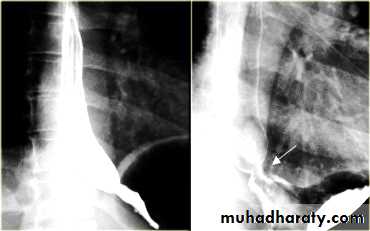

ESOPHAGEAL WEB

Thin mucosal fold (membrane)Arise from anterior wall and extend Posteriorly .>>>MCQ

Lateral view Ba. Swallow show self like filling defect with proximal dilatation.

Single or multiple

Can be congenital or acquiredMost in hypopharynx and proximal esophagus

Majority protrude from anterior esophageal wall

Symptoms if lumen > 50% compromised